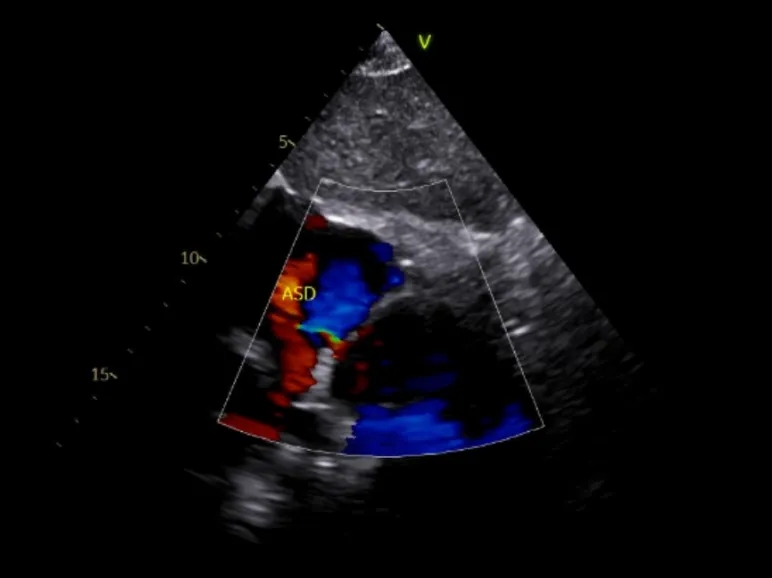

术前超声

超声所见:

1、各房室腔内径正常,大动脉内径及位置关系正常。

2、室间隔及左室后壁厚度及运动幅度正常。多切面显示房间隔中部可见宽约5mm的回声失落,多普勒示左向右分流束,流速约122cm/s,室间隔连续。

3、CDFI示三尖瓣见少量反流,流速约275cm/s,估测肺动脉收缩压约35mmHg;二尖瓣见少量反流,反流面积约1.0cm2;肺动脉瓣见小反流束。

4、心包厚度正常,心包腔内未见液性暗区。

5、心功能测值正常。

超声提示:房间隔中部回声失落,考虑:房间隔缺损;三尖瓣、二尖瓣少量反流;肺动脉轻度高压。